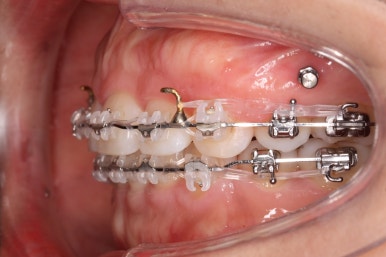

아랫니 모습입니다.

남아있는 발치의 공간이 없어졌으며 큰 이동이 없이 마무리가 되었습니다. 안쪽에는 발치공간이 다시 벌어지지 않도록 유지철사를 길게 연장해서 붙였습니다.

아래쪽의 앞니에는 잇몸뼈가 없기에 자칫 뿌리가 다 드러날 수 있는 위험한 상태였습니다.

다행히도 잇몸이 덮고 있었고 조심스레 마무리를 했기 때문에 추가적인 악화는 없었습니다. 그래도 아래앞니 쪽은 잇몸뼈가 약하기 때문에 평생 조심을 해야 한다며 거듭 말씀드리고 당부 드렸습니다.

앞니, 어금니 맞물림이 좋아진 것을 볼 수 있습니다.

안으로 굽었던 옥니의 각도가 역교정으로 다시 회복이 되었습니다.

가장 눈에 띄는 점은 윗니를 후방이동 시켰기 때문에 돌출감이 있었던 부분이 개선이 되었다는 점입니다.

앞니의 간격이 있으면 위쪽 입술은 나와보이고 아래쪽 입술은 말려 들어가는 등으로 입술선이 부자연스럽다거나 심미적으로 좋지 못하는데 이 부분이 좋아졌죠.